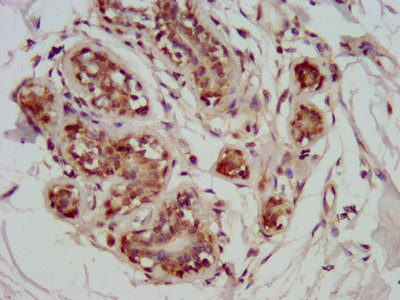

IHC image of CSB-PA803156LA01HU diluted at 1:800 and staining in paraffin-embedded human breast cancer performed on a Leica BondTM system. After dewaxing and hydration, antigen retrieval was mediated by high pressure in a citrate buffer (pH 6.0). Section was blocked with 10% normal goat serum 30min at RT. Then primary antibody (1% BSA) was incubated at 4°C overnight. The primary is detected by a biotinylated secondary antibody and visualized using an HRP conjugated SP system.